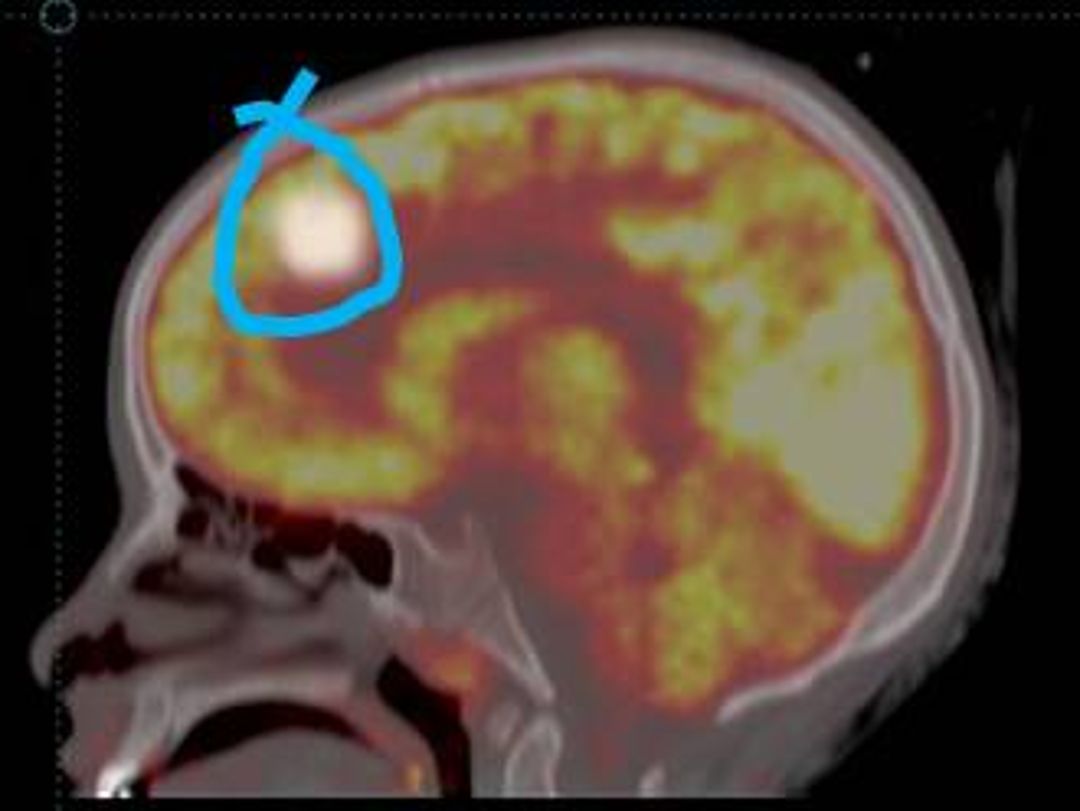

The study included 21 pediatric patients with a mean age of 5.6Yrs (range 4-16 yrs.). Of the 21 patients, 12 (57.15%) had overactive bladder with urodynamically proven DO and 9 (42.85%) had under active detrusor. In cases overactive bladder TcPTNS decreased the activity in the mid-cingulate gyrus, Hypothalamus, premotor cortex [more on right side] and Lateral pons (Figures 1a, b, c and d).

These findings were explored further as to correlate them with the neuroanatomical and physiological regions of the brain involved in the process of micturition. It is interesting to note that these are the areas which actually modulate in integrated manner during the process of bladder filling (8, 9, 11, 20, and 21).

In cases overactive bladder TcPTNS decreased the activity in the cerebellum, midbrain and adjacent midline thalamus and limbic cortical areas, i.e. the cingulate gyrus, ventromedial orbitofrontal gyrus and prefrontal cortex. These are the areas involved in the sense of bladder filling. While, FDG uptake was more avid in these areas before the start of TcPTNS. On contrary the avid uptake was noted in hypothalamus and prefrontal area in cases of underactive detrusor. These are the areas involved sensorimotor learning and the initiation of voiding.